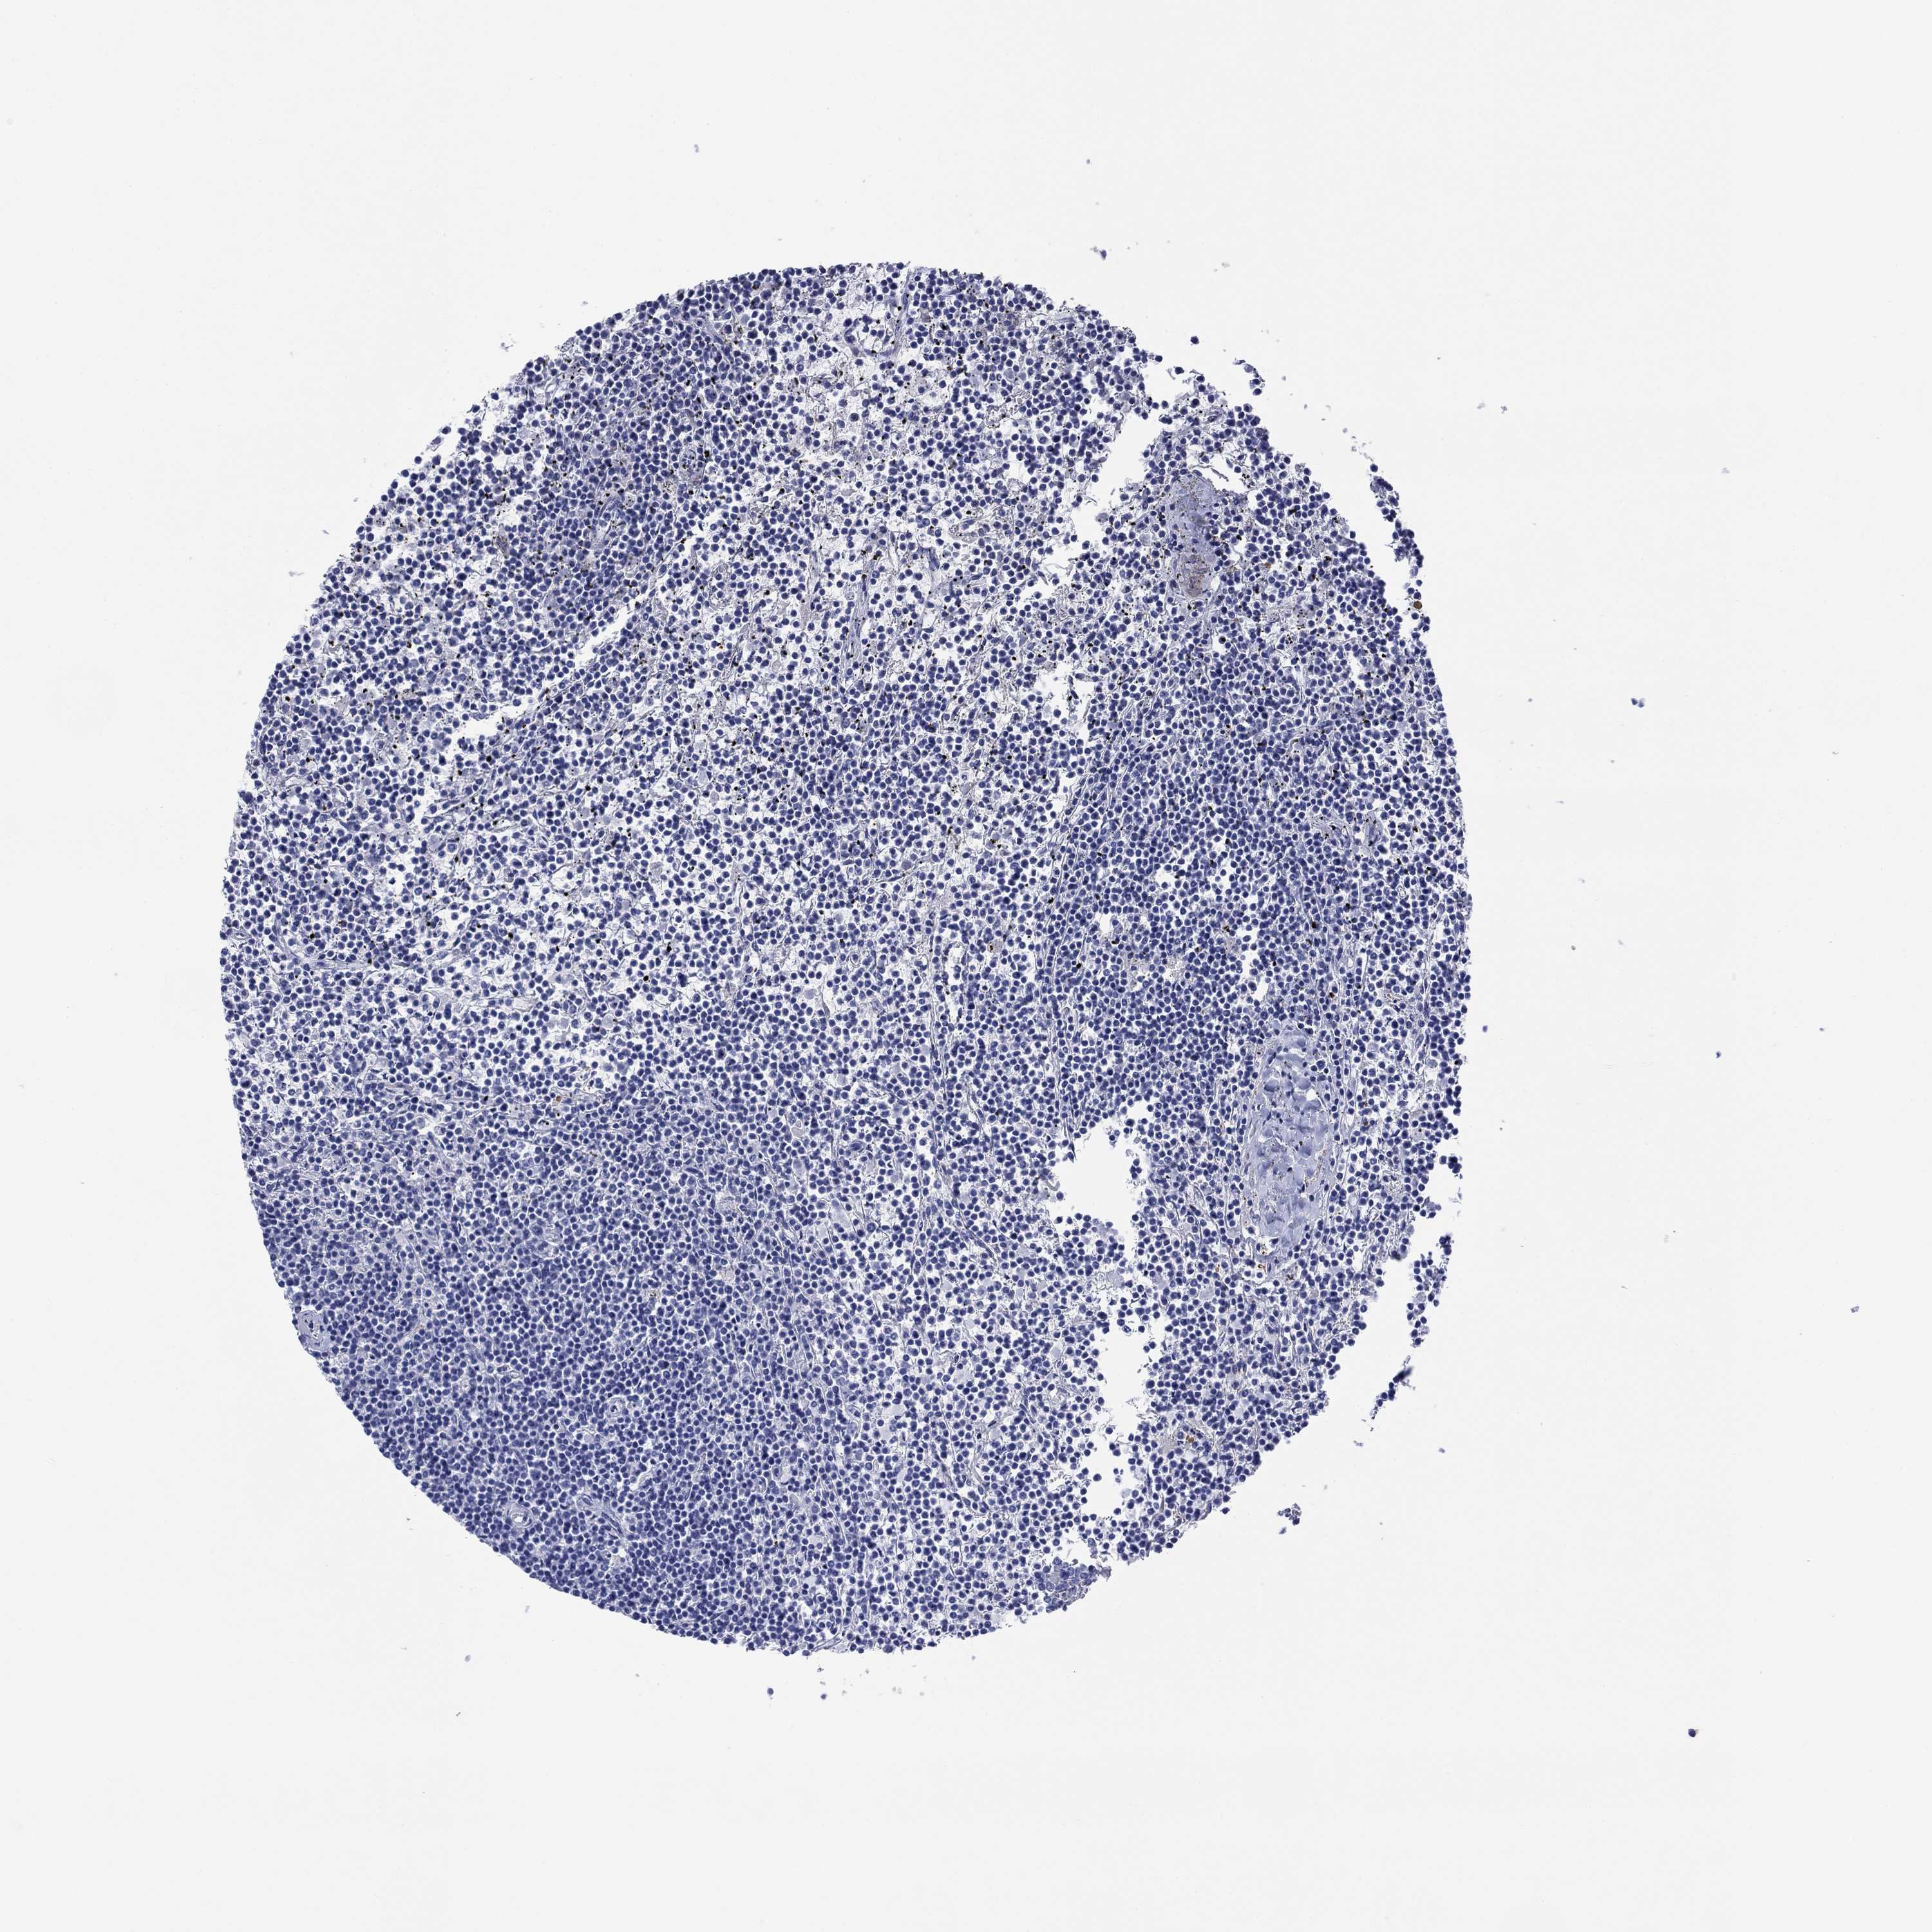

LYMPHOMA - Protein expressioni

A mouse-over function shows sample information and annotation data. Click on an image to view it in a full screen mode. Samples can be filtered based on level of antibody staining by selecting one or several of the following categories: high, medium, low and not detected. The assay and annotation is described here.

Antibody stainingi

Antibody staining in the annotated cell types in the current human tissue is reported as not detected, low, medium, or high, based on conventional immunohistochemistry profiling in selected tissues. This score is based on the combination of the staining intensity and fraction of stained cells.

Each image is clickable and will lead to virtual microscopy that enables deeper exploration of all samples and also displays staining intensity scores, fraction scores and subcellular localization as well as patient and tissue information for each sample.

Antibody HPA012911

Staining

Medium

Intensity

Moderate

Quantity

75%-25%

Location

Cytoplasmic/membranous

Malignant lymphoma, non-Hodgkin's type, Low grade